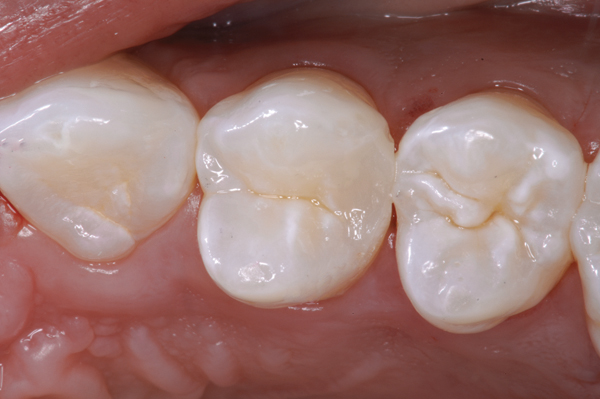

Fig 3. Minimally invasive Class II slot preparation maxillary first premolar.

Figure 3

Fig 4. Class II restoration of maxillary first premolar using a self-etch adhesive.

Figure 4